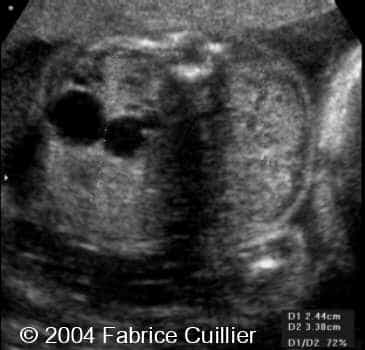

Multicystic kidney disease, unilateral, in a twin

This is a case of unilateral multicystic kidney disease in a twin with no other anomalies.